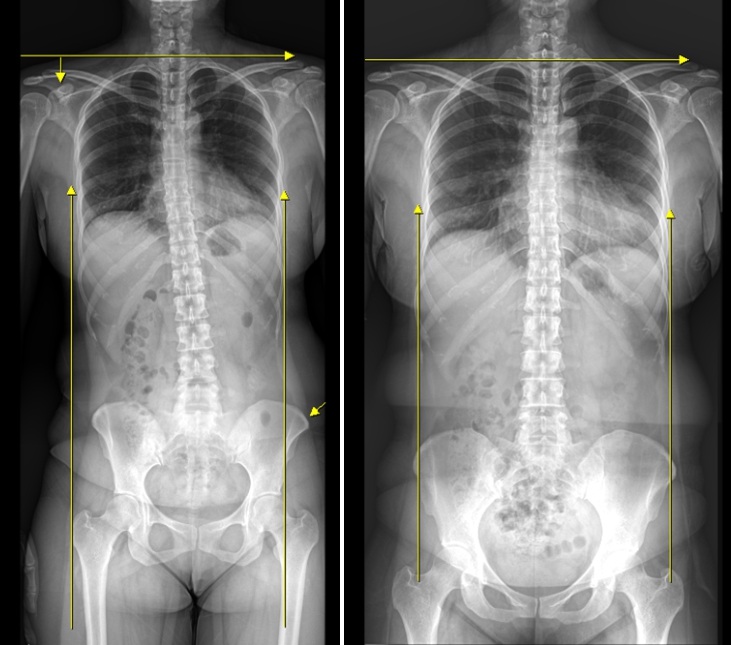

치료 전 / 후

221025~230804 약 10개월 치료

<치료 방식>

맞춤형 깔창 처방하여 보행을 바로 잡음.

추나와 도수치료로 골반교정.

봉독약침으로 염증 제거.

한약으로 신경 재생 치료 병행.

<치료 결과>

산후 요통 및 꼬리뼈 통증 감소.

요실금 증상 개선.

전반적인 체형 교정.

보행 자세 개선.

일상생활 기능 회복.

특히 요실금 증상을 가진 산모들에게서도 뚜렷한 호전을 보였으며, X-ray 검사를 통해 구조적 변화까지 확인할 수 있었습니다.